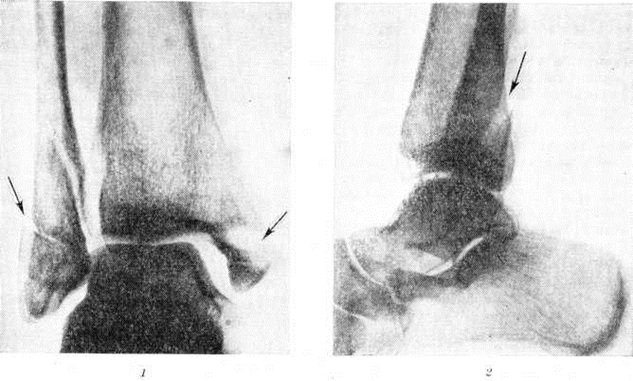

Дюпюитрена переломДюпюитрена перелом (G. Dupuytren, франц. хирург, 1777— 1835) — перелом медиальной лодыжки и малоберцовой кости в нижней трети с разрывом связок межберцового синдесмоза. При этом переломе нередко наступает подвывих стопы кнаружи. Дюпюитрена перелом встречается часто; описан Г. Дюпюитреном в 1819 год. Механизм возникновения этого перелома — пронационно-абдукционный. Стопа имеет естественную вальгусную установку, равную 10°, и поэтому она при травмах чаще подвёртывается кнаружи. При этом в силу крепости медиальной (дельтовидной) связки наступает отрывной перелом медиальной лодыжки, а таранная кость приобретает вальгусное положение. Блок таранной кости упирается в латеральную лодыжку, и происходит её перелом с разрывом передней или чаще обеих межберцовых связок. Клиническая картинаПри Дюпюитрена перелом обычно определяется припухлость в области голеностопного сустава. В случае подвывиха стопы кнаружи имеется патологический вальгусная установка стопы, особенно чётко видимая при осмотре сзади. Пальпаторно определяется резкая болезненность в области медиальной лодыжки, по ходу малоберцовой кости и в области межберцового синдесмоза. Активные и пассивные движения в суставе резко болезненны и ограничены. На рентгенограмме в прямой проекции при Дюпюитрена перелом хорошо видна линия перелома медиальной лодыжки, обычно проходящая на уровне суставной щели, а также латеральной лодыжки на уровне суставной щели или выше неё. Вместе с тем отчётливо выступают смещение отломков и возможный диастаз, то есть расхождение «вилки» сустава (рисунок 1 и 2). Для диагностики разрыва нижнего межберцового синдесмоза большое значение имеет сравнительное изучение переднезадних снимков (сделанных на одной плёнке) обоих голеностопных суставов в обычной укладке или с симметричной внутренней ротацией на 27°. Наружный подвывих стопы распознается на основании увеличения или расширения щели между суставным контуром медиальной лодыжки и прилежащей к ней суставным краем таранной кости, в норме равной ширине остальной части суставной щели голеностопного сустава. На боковой рентгенограмме обычно отчётливо видна плоскость перелома малоберцовой кости и характер смещения отломков. Линия перелома чаще всего имеет косое направление сверху вниз и сзади наперёд, а сам перелом — оскольчатый и нередко является внесуставным. Кроме этого, на боковой рентгенограмме обычно виден характер смещения медиальной лодыжки. Тщательного изучения требует снимок в боковой проекции для распознавания перелома переднего или заднего края эпифиза большеберцовой кости и соответствующего подвывиха стопы в голеностопном суставе, что очень важно для правильной репозиции отломков. |